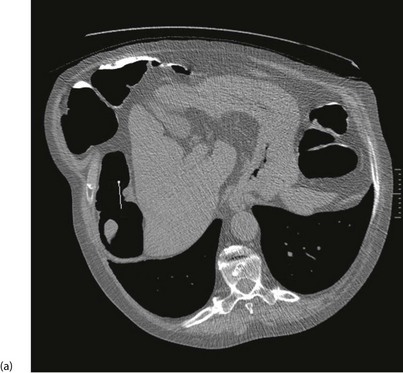

Plain abdominal radiology: Most abdominal films are taken with the patient supine. Bowel is visible when it contains gas (Figs 5.3 and 5.4); normal small bowel is less than 3 cm wide and tends to occupy the centre of the abdomen. When dilated, it shows transverse folds (plicae circulares) which completely cross the lumen. The colon usually lies peripherally and has haustrations; these folds only partly traverse the lumen (Fig. 5.3). Normal colon is less than 6 cm wide and often contains faecal lumps with a mottled appearance. Further reading about this topic is available from: http://www.studentbmj.com/topics/clinical/imaging_techniques.php.